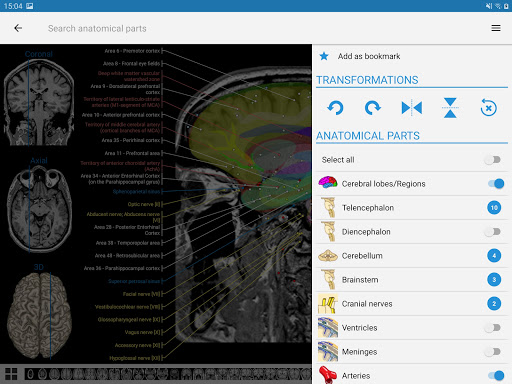

*Improved detail view of anatomical parts for easier identification in images of the current and other modules.

-You can now use the settings menu and scroll through images at the same time on tablets

New : You can now filter the modules by region or by content type so you can find the module you are looking for much faster.

- You can now hide structures one by one (new button inside the description popup) and display them again in the right menu